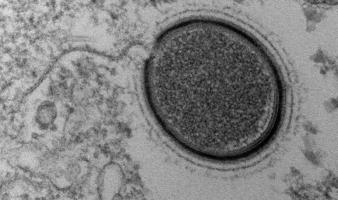

Virus